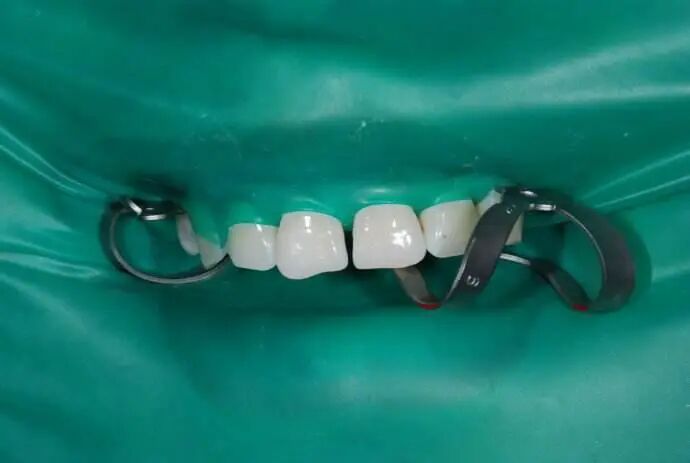

橡皮障,就是一张隔水且有弹性的橡皮布。根据实际治疗的需要,牙医会将其打孔、夹置,随后套在牙颈部,使牙齿与口腔环境相隔离。橡皮障不仅可以避免治疗时的异物落入口腔,同时也能减少气溶胶微粒的扩散,降低感染风险,还可以保持治疗器械的干燥清爽,方便牙医操作。